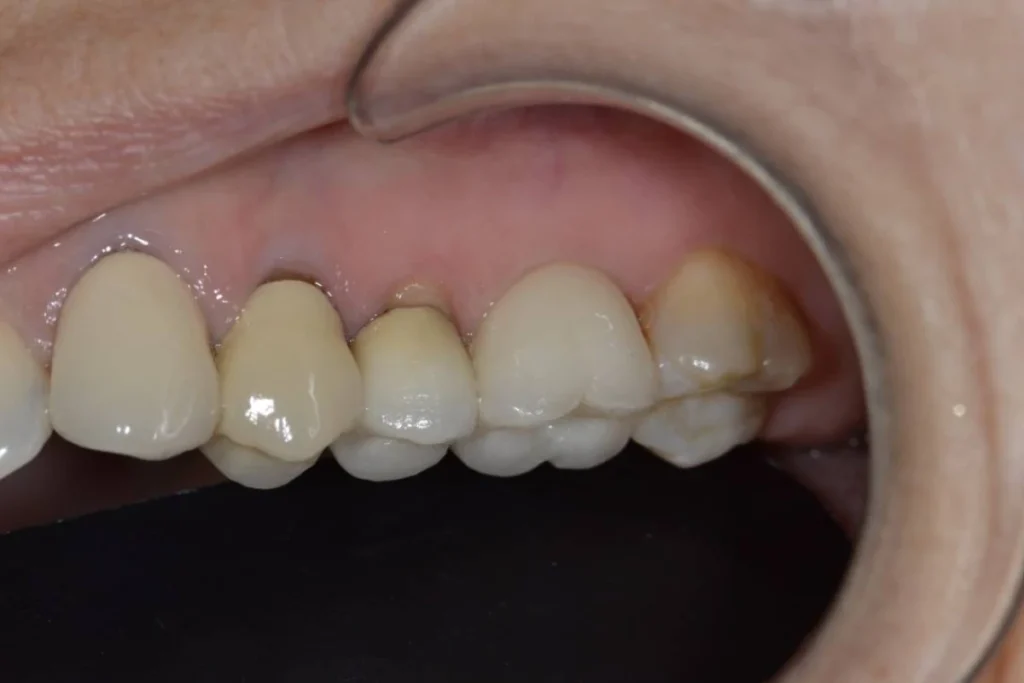

Nous vous présentons le cas de Mme B. 53 ans, qui consulte suite à des douleurs sur sa molaire supérieure gauche.

Après un examen clinique et radiographique, le verdict tombe… la dent n’est malheureusement plus conservable.

Après lui avoir exposé les différentes solutions, Madame B. souhaite remplacer sa dent par un implant. C’est la solution de choix pour retrouver une dent fixe sans avoir à abimer les dents de part et d’autre. L’analyse du scanner nous permet de proposer à Madame B. une extraction implantation immédiate. Il s’agit de réaliser en une seule et même séance l’extraction de la dent condamnée et la mise en place de l’implant dentaire.

Cela permet d’éviter une 2ème chirurgie à notre patiente et de raccourcir la durée du traitement de plusieurs mois. Un comblement osseux est réalisé le jour de l’intervention.

3 mois après la pose de l’implant, la patiente peut retrouver une dent fonctionnelle et esthétique.